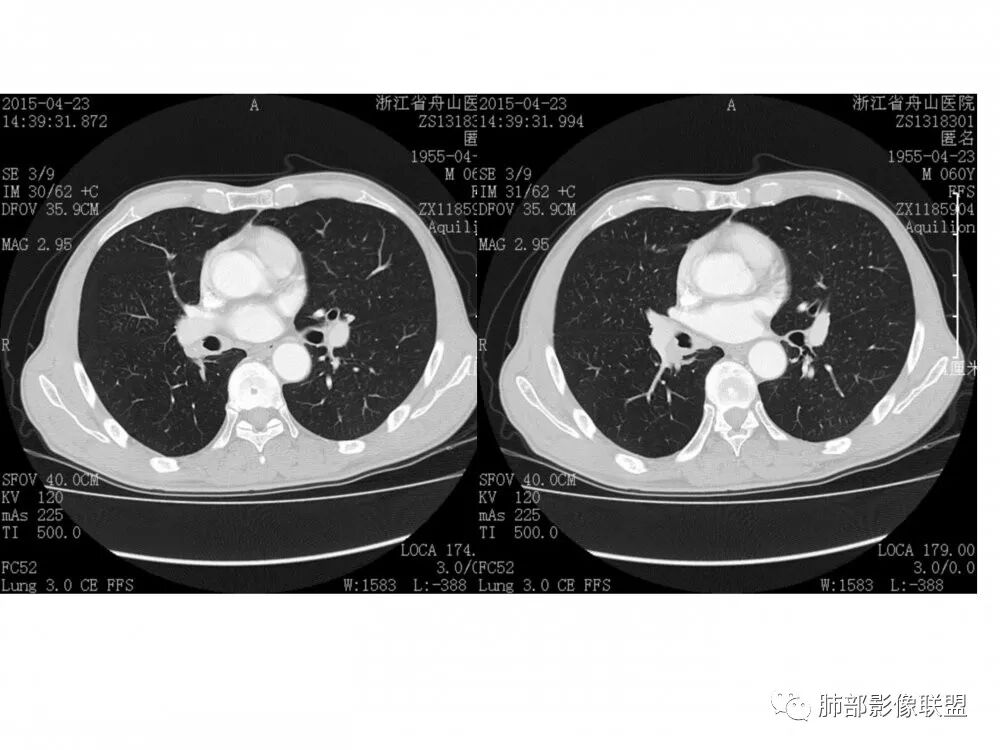

老年男性,右肺下叶支气管腔狭窄,见低强化软组织密度结节突向腔内,局部支气管壁破坏消失,邻近血管受压推移,纵膈内及右肺门区淋巴结肿大。综合考虑小细胞肺癌(SCLC)可能性大,鉴别类癌及鳞癌。

老年男性,右肺下叶支气管腔内可见软组织密度影,向腔内突入,支气管壁破坏,向外突出,管腔明显狭窄,增强后轻度强化,伴纵膈及肺门多发肿大淋巴结,首先考虑恶性肿瘤,小细胞肺癌可能大,建议支气管镜检查

右肺下叶背段支气管腔内软组织影,管腔截断,管壁增厚,临近肺动脉壁毛糙,气管软骨环破坏向外侵及,4R区及肺门肿大淋巴结,恶性,小细胞?类癌?鳞癌?粘液表皮样癌? 考虑小细胞。

右中间、右下叶背段支气管管腔内见突向管内的管状软组织影,相邻支气管壁有侵犯,增强有强化,纵隔2R 、4R、10R组淋巴结肿大,增强有强化,未见ct值,常规考虑恶性肿瘤,小细胞癌并同侧纵隔淋巴结转移,鳞癌、类癌街排,建议支气管镜检查。

右肺下叶支气管开口新生物,轴位管腔及纵向基底干大部分受累狭窄,支气管管壁破坏并突破形成腔外肿块,血管累及变细,肉眼观轻度强化,右肺门、纵膈淋巴结肿大,恶性没问题,阻塞性炎症不明显,类癌强化明显不支持,老年男性,首先考虑小细胞癌,鉴别不典型鳞癌和腺癌。